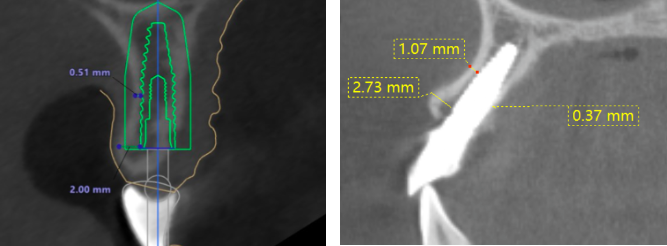

影像学检查

骨宽度稍欠,骨宽度约4.0mm,骨高度约15mm

术前术后对比,22根方偏唇侧:

12牙

22牙

偏斜可能原因:腭侧皮质骨阻力较大,使钻针往唇侧偏斜